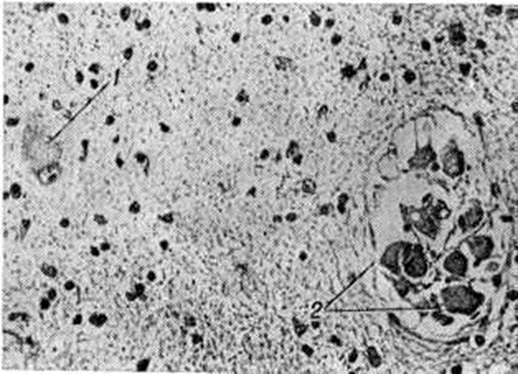

Туберозный склерозТуберозный склероз (sclerosis tuberosa; латынь tuberosus бугристый; склероз; синонимы: болезнь Бурневилля, болезнь Бурневилля — Прингла) — наследственное прогрессирующее заболевание из группы факоматозов, характеризующееся сочетанным поражением нервной системы, кожи, глаз, костной и эндокринной систем, внутренних органов. Впервые описан в 1863 год Ф. Реклингхаузеком. В 1880 год Бурневилль (D.-M. Bourneville), выделив это заболевание в отдельную нозологическую форму, ввёл термин туберозный склероз и детально описал ранние неврологический симптомы, изменения кожи и другие В 1890 год Прингл (J. J. Pringle) подробно изучил аденомы сальных желёз кожи лица и подчеркнул, что они характерны для Туберозный склероз По данным Пенроуза (L. S. Penrose), Туберозный склероз в общей популяции встречается с частотой примерно 1:600 000, среди больных с различной степенью умственной отсталости — 1:30 000. Этиология. В развитии Туберозный склероз большую роль отводят генетическим факторам. Семейные формы заболевания нередко наблюдаются в нескольких поколениях. Наследуется Туберозный склероз по аутосомно-доминантному типу с неполной пенетрантностью мутантного гена (смотри полный свод знаний: Пенетрантность гена). Близнецовый метод (смотри полный свод знаний) исследования обнаруживает высокую конкордантность по признакам болезни у монозиготных близнецов. Патогенез. Предполагается, что в основе заболевания лежит генетически обусловленное нарушение развития зародышевых клеток, приводящее к эктомезодермальным дисплазиям с образованием склонных к неопластической трансформации опухолевидных узлов в центральная нервная система и внутренних органах. Патологическая анатомия. Головной мозг при Туберозный склероз обычно увеличен по сравнению с возрастной нормой, однако иногда наблюдают и микроцефалию (смотри полный свод знаний). Кора головного мозга на отдельных различной величины участках белесовато-желтоватого цвета и большей, по сравнению с окружающей тканью, плотности. В центре участков изменённой коры имеются неглубокие западения, в которые погружаются сосуды. На разрезах полушарий головного мозга в коре обнаруживается различное количество грибовидных опухолеподобных образований, или бугров (рисунок 1); выявление их легло в основу названия заболевания. Единичные или множественные сероватые бугорки размером от булавочной головки до нескольких сантиметров в диаметре также обнаруживают в белом веществе полушарий головного мозга, в боковых желудочках, чаще вблизи ленты таламуса, реже в передних и нижних рогах боковых желудочков, в сильвиевом водопроводе (водопровод среднего мозга) и в четвёртом желудочке. В некоторых случаях Туберозный склероз изменения имеются и в мозжечке. Опухолеподобные образования могут нарушать отток цереброспинальной жидкости из желудочков и приводить к развитию внутренней гидроцефалии (смотри полный свод знаний). Эти образования обычно обызвествлёны, причём очаги обызвествления расположены чаще в глубине бугра. При гистологический исследовании туберозных участков в коре головного мозга обнаруживают атипичные, причудливой формы крупные нейроны (рисунок 2), аксоны которых нередко направляются к поверхности коры, сплетаются в клубки, внедряются в стенки сосудов. В коре обнаруживают и крупные атипичные клетки с одним-двумя пузырьковидными ядрами, цитоплазма которых при окрашивании тионином приобретает бледно-голубую окраску. Эти клетки, как установлено современными иммунологический исследованиями, также являются нейронами, а не астроцитами, как предполагалось ранее. В коре головного мозга имеются и нарушения нормальной цитоархитектоники с отсутствием нейронов, их атрофией и вакуолизацией. Кора головного мозга нечётко отграничена от белого вещества, в ней определяются выраженный глиоз (смотри полный свод знаний), аргентофильные образования, зернистые шары, расположенные по ходу сосудов (появление зернистых шаров некоторые исследователи связывают с деструктивными процессами, обусловленными частыми эпилептическими припадками). Стенки сосудов мозга утолщены, отмечаются признаки фиброза и гиалиноза (смотри полный свод знаний). Мягкая и паутинная оболочки головного мозга утолщены, в последней увеличено количество меланофоров. |

Рис. 1. | ||